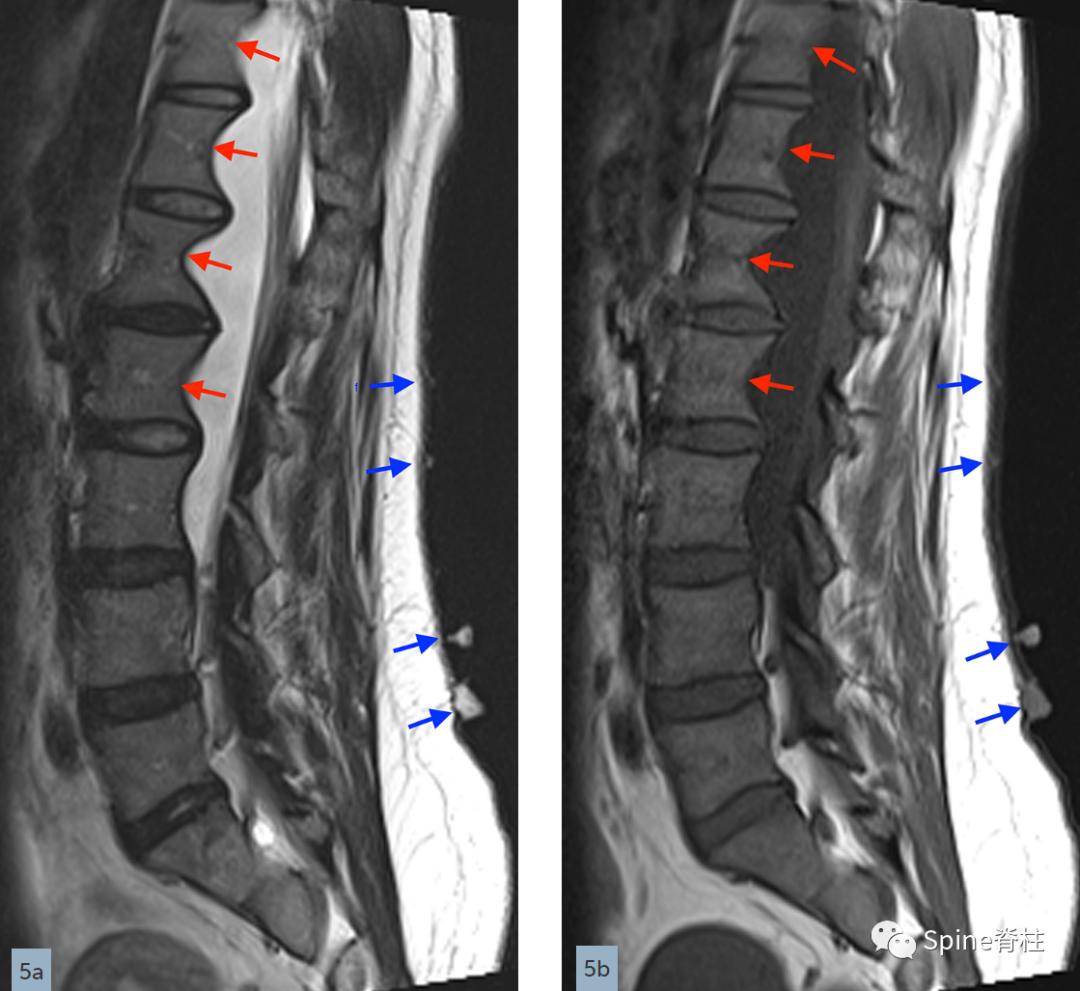

矢状位T2(a)和T1(b)加权像提示下胸椎和上腰椎硬膜扩张伴显著的椎体后壁扇形凹陷(红色箭头)。轴位T2(c)和T1(d)加权像提示硬膜囊外侧膨出(绿色箭头)伴椎体扇形缺损。蓝色箭头是指继发于皮肤神经纤维瘤的多发性皮肤结节